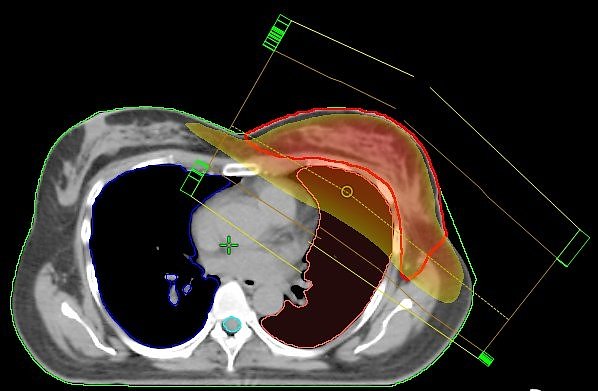

Normal: Stehfeldtechnik mit 2 Feldern (Standardtechnik); der Hochdosisbereich erfasst nicht nur das Zielvolumen (rote Kontur), sondern auch die umgebenden Risikoorgane (Lunge und Herzkranzgefäße), was zu Nebenwirkungen führen kann

Parallel zur Zertifizierung wurde in der Klinik für Radioonkologie und Strahlentherapie ein kleines Jubiläum gefeiert. In der vergangenen Woche wurde die 1200. Brust-Tumor-Patientin nach einer Methode bestrahlt, die es bundesweit so nur in Nordhausen gibt. Bei der herkömmlichen Bestrahlung der Brust werden in den überwiegenden Fällen auch Teile der Lunge oder die Herzkranzarterien in Mitleidenschaft gezogen.

Die seit dem Jahr 2009 im Südharz Klinikum eingesetzte Bestrahlungstechnik an den Linearbeschleunigern macht es möglich, den Bereich der Bestrahlung nicht nur geradlinig, sondern auch bogenförmig maßgeschneidert zu erfassen.